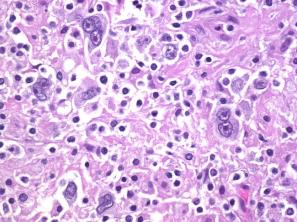

Hodgkin`s lymphoma

owl's eye appearance dx Hodgkins lymphoma

Hodgkin

Hodgkin lymphoma